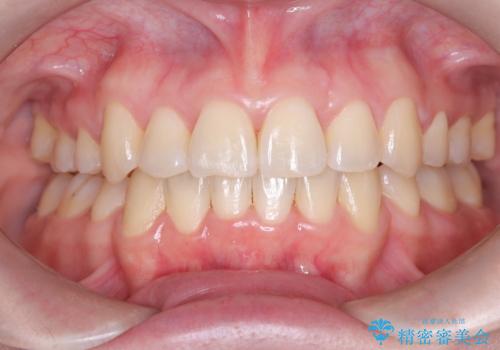

【ワイヤー矯正】八重歯 歯のでこぼこを治したい!